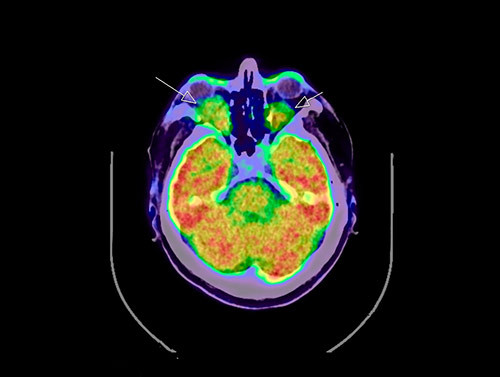

18FDG PET-CT viste økt opptak perirenalt, oppfyllinger i begge orbitae, periaortalt, i myokard og i oppfylling rundt hjertet samt i beinmargen i distale deler av begge femora og proksimale tibiae (fig 3, fig 4). I nyrene var det dilatasjon av calyces, men ikke dilatasjon av det ekstrarenale nyrebekken eller uretre. Ultralyddoppler av nyrearterier viste ikke tegn på nyrearteriestenose. I lungene var det lette mattglassfortetninger og sparsom bilateral pleuraeffusjon. Spirometri viste lett redusert belgfunksjon av restriktiv type. Ekkokardiografi viste grensestor venstre ventrikkel med god venstre og høyre ventrikkelfunksjon, i tillegg til lett perikardvæskebrem på 0,5 – 0,6 cm uten hemodynamisk betydning.

Røntgenundersøkelse av de lange rørknoklene viste symmetrisk utbredt sklerose i diafyser og metafyser, med utsparing av epifysene i radius, ulna, femur og tibia (fig 5). I tillegg var det tegn til periostitt, mest uttalt i femur og i tibia. Ved skjelettscintigrafi var det kraftig aktivitetsopptak i distale del av femur, proksimale og distale del av tibia, distale del av radius og i maksillen bilateralt (fig 6). Endokrinolog fant ikke holdepunkter for diabetes insipidus eller andre endokrine forstyrrelser.

Sykdommen rammer menn hyppigere enn kvinner, og gjennomsnittlig debutalder er 55 år (16 – 80 år) (5). Mange organer kan bli affisert av sykdommen (tab 1) (5, 6). Nesten alle pasienter med Erdheim-Chesters sykdom har affeksjon av skjelettet, men bare omkring halvparten har symptomer på dette og da som oftest som smerter i knær og ankler. Typiske radiologiske funn er bilateral og symmetrisk osteosklerose i diafysen og metafysen til de lange rørknoklene, oftest i underekstremitetene. 99technetiumskjelettscintigrafi og 18FDG PET-skann vil vise økt opptak i disse områdene (7) – (9).

Til forskjell fra langerhanscellehistiocytose ser man vanligvis ikke affeksjon av det aksiale skjelettet ved Erdheim-Chesters sykdom (7). Ved langerhanscellehistiocytose er det som regel osteolytiske lesjoner i skjelettet og sjelden affeksjon av de lange rørknoklene (7). Vår pasient hadde typiske funn i skjelettet, påvist ved både scintigrafi, røntgenundersøkelse og PET-skann.